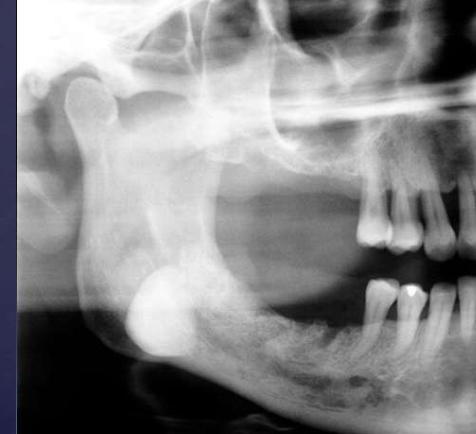

describe the ameloblastoma in this radiograph

multilocular w/ coarse septae

thinning of inferior mand border

displacement of teeth + IAN